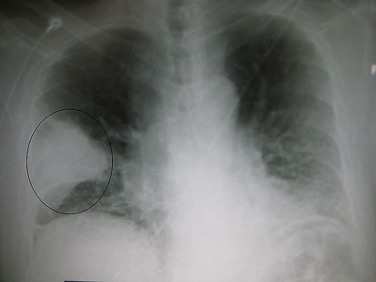

¿Cómo se ve la neumonía?

Rayos X de tórax donde se observa neumonía complicada en el lóbulo inferior derecho con efusión.